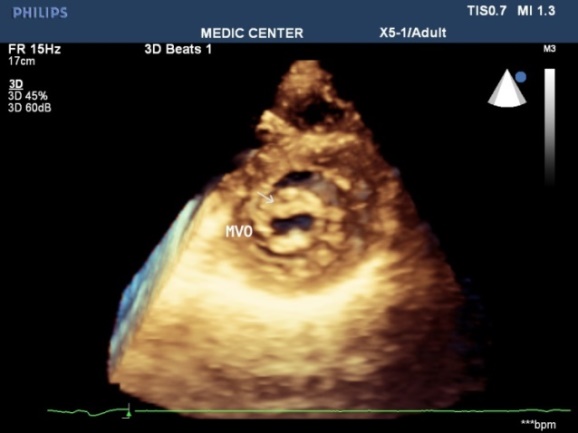

MVA3D measured by Real-Time 3DTEE to compare with conventional two-dimensional planimetry MVA2D.The 3D Assessment was significantly smaller the 2D planimetry: MVA3D = 0.95cm2 ± 0.21; MVA2D =1.16cm2 ± 0.24; mean diffence=-0.21cm2, n=327, p<0,001.

Some patients with high Wilkins score evaluated by 2DTEE still have responded well to Balloon Mitral Valvuloplasty. Real-time three-dimensional transesophageal echocardiography provides important informations regarding the involvement of rheumatic process on the mitral valve, particularly the symmetry length of commissural fusion. Furthemore RT-3DTEE also shows the thickening, the fibrosis and the calcification of the whole mitral commissures that cannot be visualized by 2DTEE. The 3D image allows superior visualization of the thickening of the mitral leaflet, particularly the commissures.

The 3DTEE usually details the subvalvular apparatus not appreciated on 2DTEE while studying the leaflets.

Direct planimetry of mitral valve orifice by 3DTEE is the gold standard method now. The cropping function ensures that the orifice area is traced in a plan that is at the tip of the mitral valve (Figures 2-17).

Figure 13. RT-3DTEE shows small and restrited mitral orifice, commissural  fusion, extensive rheumatic  nodules, severe deformity of mitral leaflets

Figure 14. Zoom 3DTEE image  visualizing the thickenned leaflets, commissural fusion,  nodules of rheumatic fever